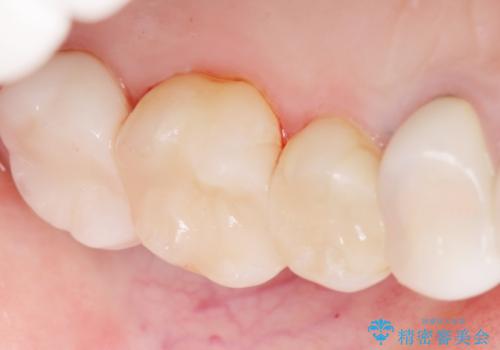

銀歯の下が虫歯になっている セラミックインレー 30代女性

- 奥歯がたまにしみることを主訴に来院された患者様です。

精査したところ、奥歯のメタルインレー(銀の詰め物)の下でう蝕が広がっていました。

う蝕を丁寧に除去したのち、セラミックインレーによる補綴治療を行いました。